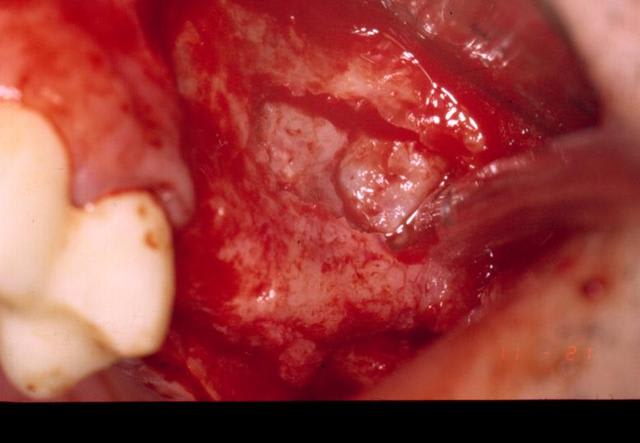

et encore

Comblement aujlvz - Eugenol

Alhoun qu'utilise tu comme comblement?

merci les gars. dans ce cas, et presque tous mes sinus, c'est du bio-oss à 100%.

ayant posé des branemark pendant des années, je n'aurai effectivement jamais osé faire ça avec une structure purement cylindrique, le grip du micro-thread conique est vraiment sympa et rassurant. quant au rapport diamètre longueur, généralement c'est entre 13 et 15 dans un sinus. là, le diamètre du col est 4.5, et le diamètre du fût est de 3,5. échaudé par mon expérience et celle de quelques copains avec les implants trop larges, et par intuition, mais il doit y avoir de la litérature, je pense que la micro-circulation se rétablit plus facilement et plus rapidement autour de diamètres moins importants.